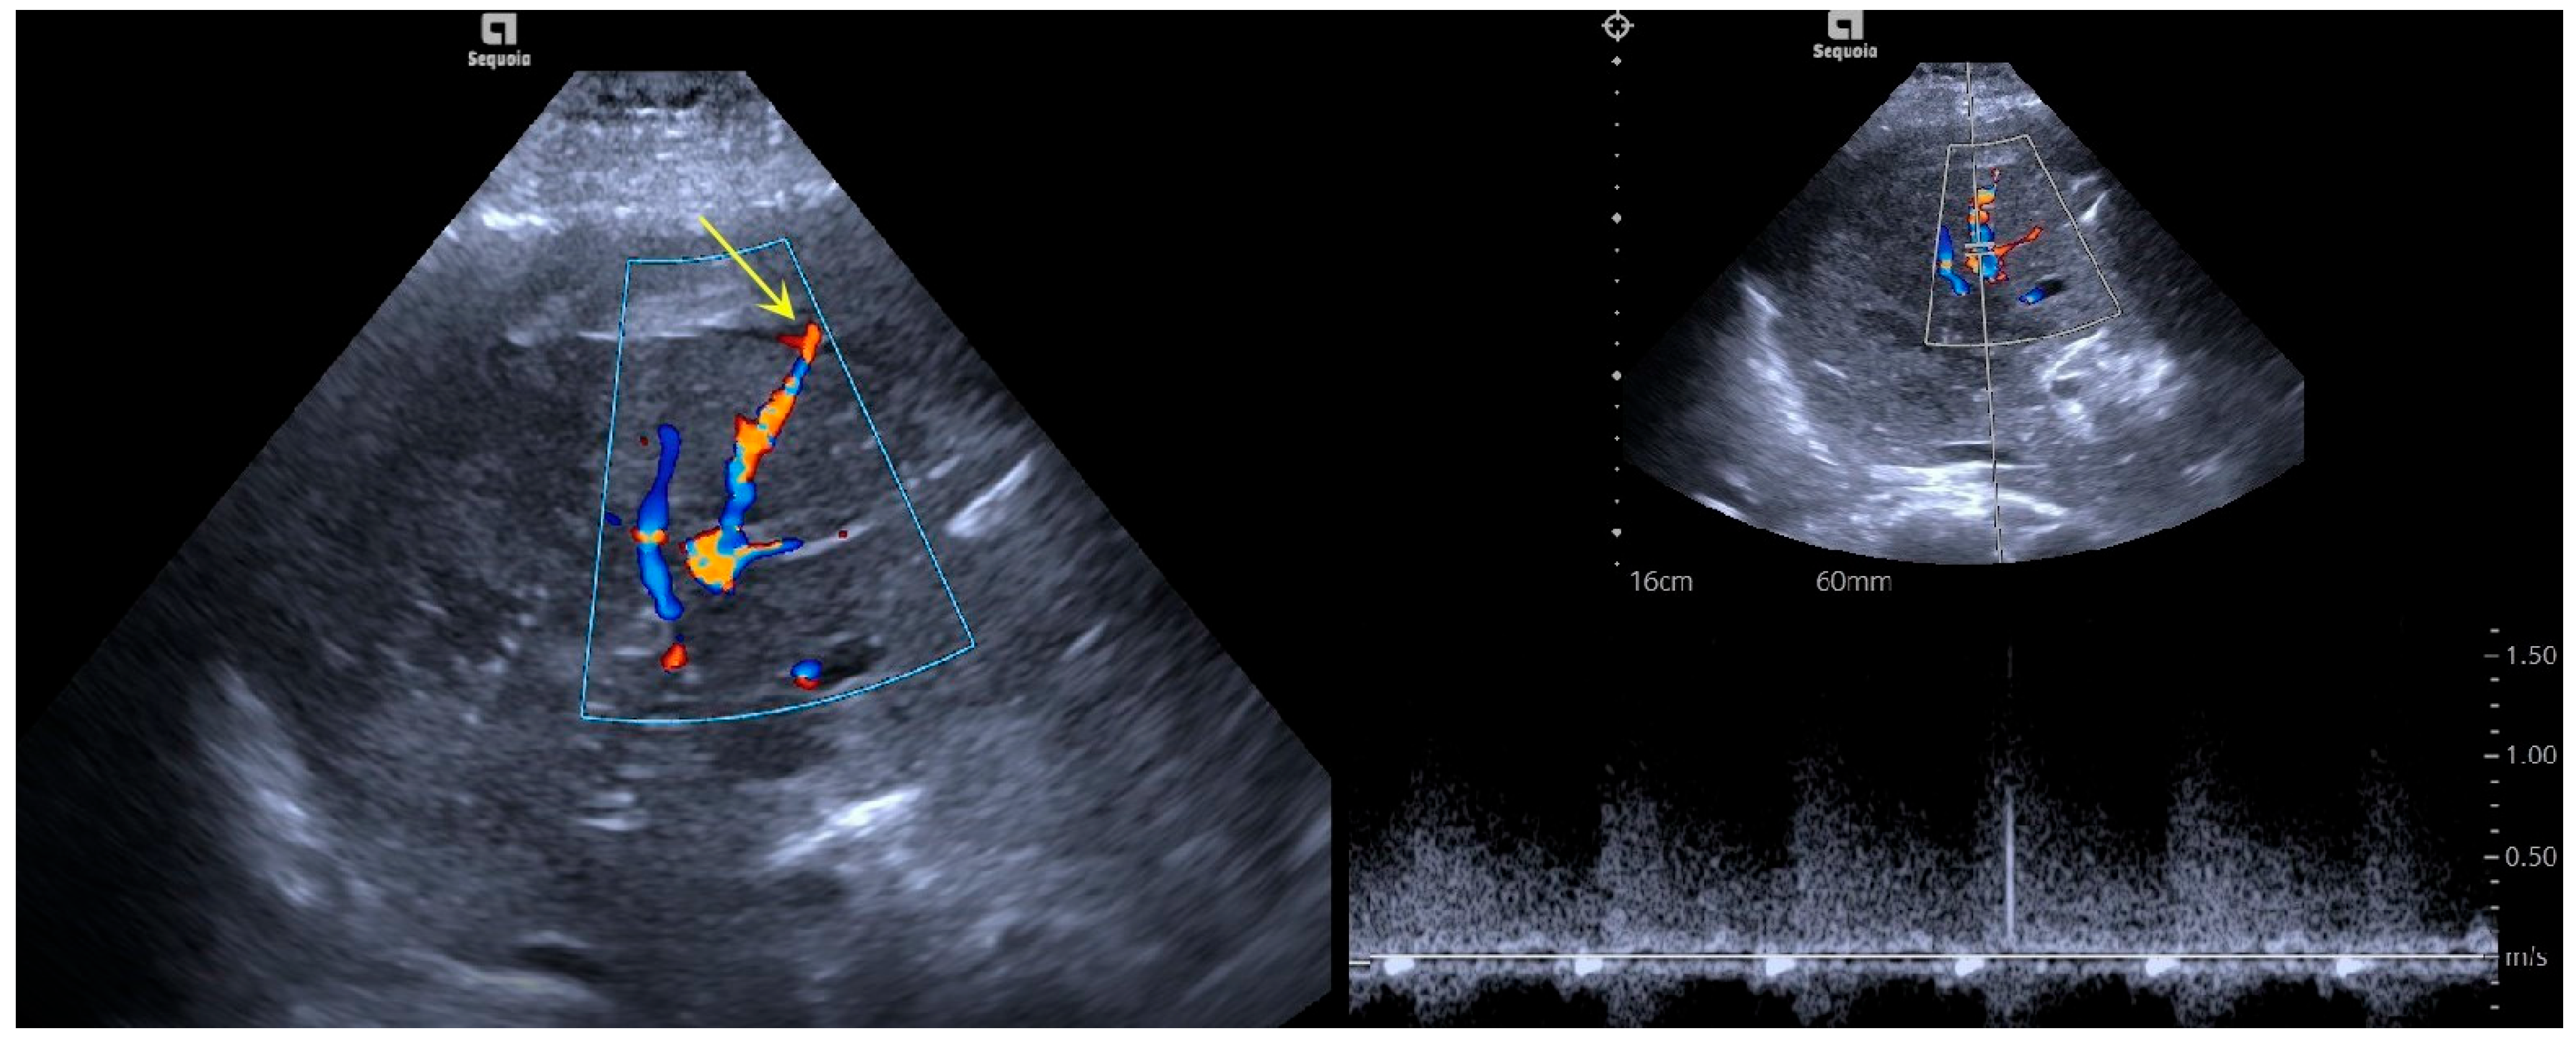

3.1. Imaging Features